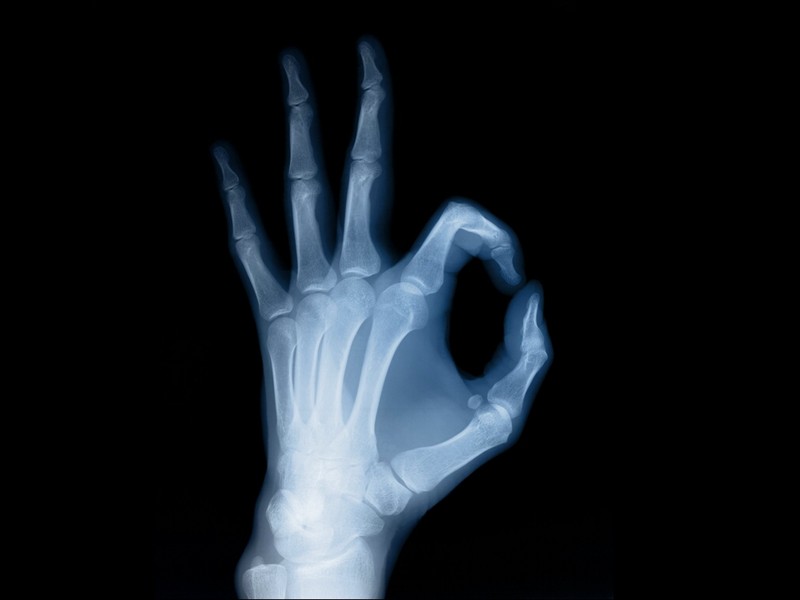

X光:像把面包压扁了看。X光能够穿过人体,遇到被遮挡的部位,底片上不会曝光,洗片后这个部位就是白色的。就像一片面包用手压瘪了,里面的纹理纤维会清晰一些。X光有个最大缺是深浅组织的影像相互重叠和隐藏,有时需要多次多角度拍摄X光片。外伤中,如果怀疑伤到了骨头,优先选择X光。拍胸片也可以粗略检查大部分脏器的情况。

CT:像把面包切片看。CT是基于X光分层穿过人体,再经过电脑计算后二次成像,就像把面包切成片来看。优点是经计算后可以分层看,能显示出更多的组织信息。如果需要进一步观察骨头外伤,可以选择CT。